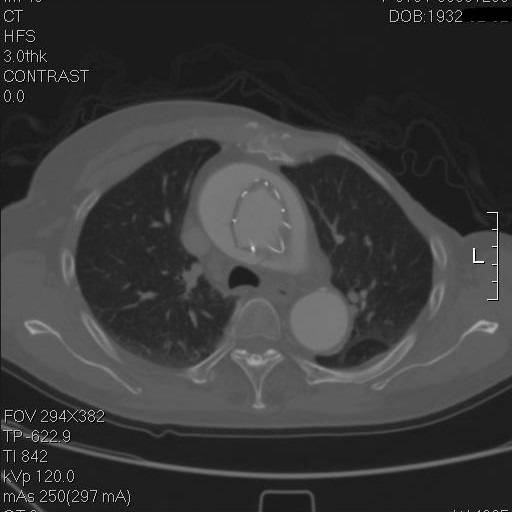

这个层面,支架终于完全在真腔内了,但假腔基本没有闭合。

到弓部可以看到,支架远端贴得倒还可以